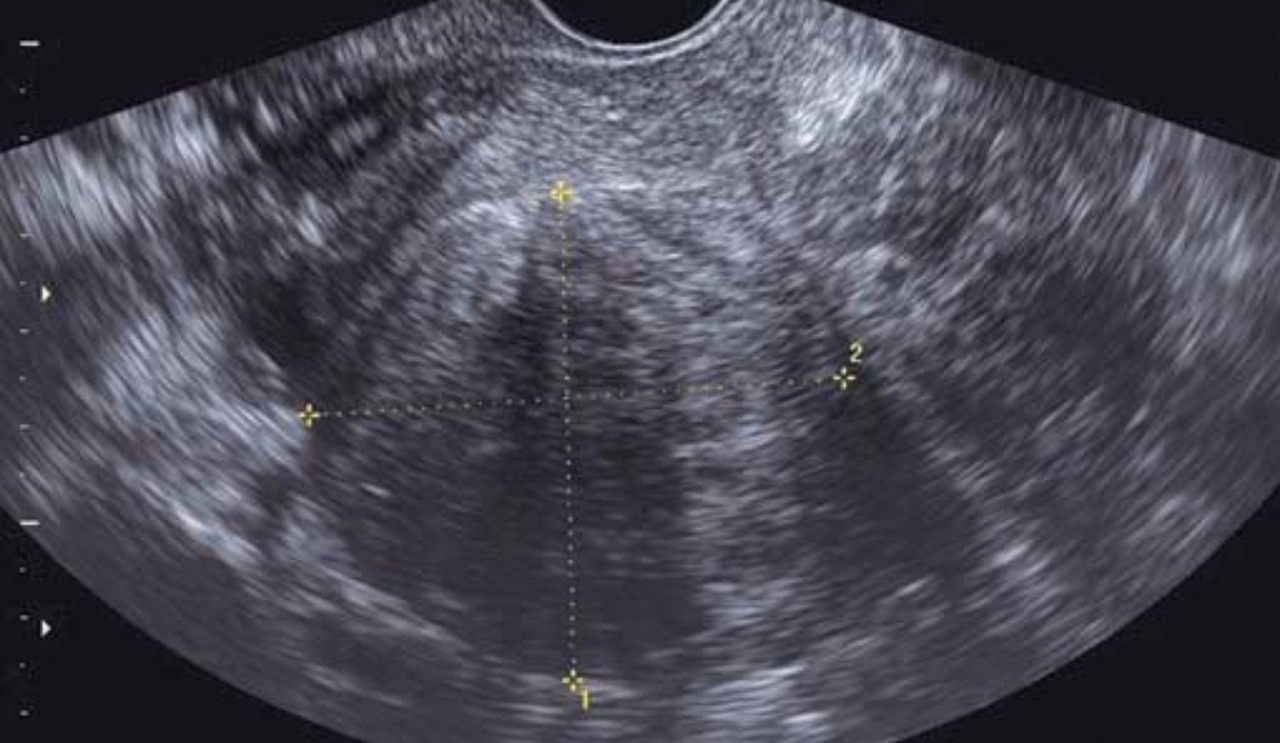

L’hyperplasie de l’endomètre correspond à des anomalies structurales endométriales aux frontières de la bénignité et de la malignité. Le diagnostic est histologique. On retrouve à l’échographie un endomètre épaissi (fig. 7). L’hystéroscopie met en évidence un endomètre épais et permet de diriger les biopsies. La classification de l’Organisation mondiale de la santé (OMS) de 1994, reconduite en 2003, subdivisait les hyperplasies endométriales en quatre groupes : les hyperplasies simples sans atypies, les hyperplasies complexes sans atypies, les hyperplasies simples avec atypies et les hyperplasies complexes avec atypies. La classification de l’OMS de 2014, reconduite en 2020, a simplifié cette classification et conservé uniquement deux groupes : les hyperplasies endométriales sans atypies et les hyperplasies endométriales avec atypies/EIN (Endometrioid intraepithelial neoplasia). Il a été démontré qu’hyperplasie atypique et EIN étaient sensiblement synonymes.

Le cancer de l’endomètre est la première cause à évoquer en cas de métrorragies post-ménopausiques. Ces métrorragies sont spontanées, indolores et de faible abondance. Il s’agit en général d’un adénocarcinome. L’interrogatoire recherche des facteurs de risque généraux (âge, diabète, hypertension artérielle [HTA], obésité), locaux (irradiation pelvienne, hyperplasie adénomateuse ou atypique) ou hormonaux (puberté précoce, ménopause tardive, nulliparité, estrogénothérapie de traitement hormonal substitutif, prise de tamoxifène). L’examen retrouve un utérus modérément augmenté de taille. Le diagnostic repose sur l’histologie. On peut réaliser une biopsie d’endomètre en consultation à la pipelle de Cormier ou à la canule de Novak qui n’a de valeur que si elle est positive. Le prélèvement histologique peut aussi être réalisé par curetage bio­psique ou sous hystéroscopie, permettant la visualisation directe des lésions et le guidage des prélèvements histologiques par résection. L’échographie pelvienne recherche un épaississement de l’endomètre (mesure des deux feuillets supérieure à 4 mm) ainsi qu’une irrégularité de celui-ci, avec une mauvaise visualisation de l’interface endomètre-myomètre.